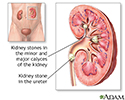

Nephrolithiasis - illustration

Nephrolithiasis

illustration